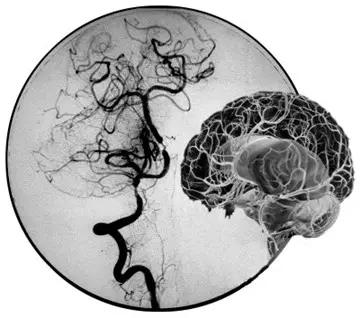

DSA圖片上提示顱底血管煙霧現(xiàn)象

“煙霧病”,原本是起源于日本的一類疾病,又稱“Moyamoya病”或“腦底異常血管網(wǎng)癥”,是一組以頸內(nèi)動(dòng)脈虹吸段及大腦前、中動(dòng)脈起始部狹窄或閉塞,腦底出現(xiàn)異常的小血管網(wǎng)為特點(diǎn)的腦血管病。因腦血管造影時(shí)呈現(xiàn)許多密集成堆的小血管影,似吸煙時(shí)吐出的煙霧,故名煙霧病。

目前明確的病因明確,跟遺傳有關(guān),可能有與后天血管的變態(tài)炎癥反應(yīng)有關(guān)。主要臨床癥狀有表現(xiàn)為“缺血性腦卒中”和“出血性腦卒中”的臨床癥狀,還可表現(xiàn)為癲癇發(fā)作。病程發(fā)作復(fù)雜多變,可反復(fù)發(fā)作并發(fā)作規(guī)律不可預(yù)測(cè),預(yù)后較差。診斷主要可通過(guò)頭顱MRA(注:磁共振血管造影)或CTA(注:CT血管造影)確診,最能明確診斷是腦血管DSA(注:Digital Subtraction Angiography,血管造影)檢查,發(fā)現(xiàn)頸內(nèi)動(dòng)脈末端及大腦前、中動(dòng)脈起始端狹窄或閉塞,并見顱底出現(xiàn)明顯異常的小血管網(wǎng)。可通過(guò)手術(shù)或內(nèi)科的藥物治療,但效果欠佳,易反復(fù)發(fā)作。

提到煙霧病這個(gè)新鮮的詞匯,很多人可能要和抽煙連在一起,其實(shí)兩者根本就不相關(guān)。“之所以叫煙霧病,其實(shí)是一個(gè)形象描述大腦像煙霧狀的小血管的特征。”暨南大學(xué)附屬第一醫(yī)院神經(jīng)外科王向宇主任告訴記者,發(fā)生煙霧病時(shí),腦內(nèi)主要血管會(huì)因各種不明確原因(如遺傳、感染、血管炎、青少年動(dòng)脈粥樣硬化、放射治療等)變得狹窄甚至阻塞,導(dǎo)致腦缺血。這時(shí)大腦為了拯救因缺血而逐漸枯萎的神經(jīng)元,就會(huì)從已經(jīng)變狹窄的大血管上生出小血管來(lái)緩解缺血狀況,這些小血管交叉成網(wǎng)狀,一旦做數(shù)字剪影血管造影檢查,醫(yī)生就會(huì)發(fā)現(xiàn)像吸煙時(shí)噴出的煙霧狀血管網(wǎng),為此稱為“煙霧病”。